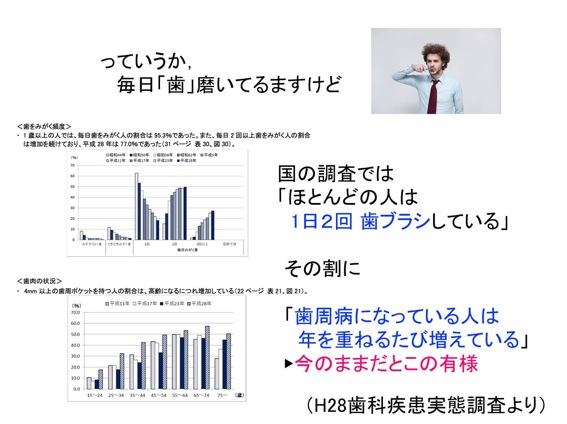

基本的には、毎日歯を磨くということが大前提です。ただ1日に歯を2回磨く日本人が大多数なのに、歯周病の人は80%なので、前にお話しした(連載の第1回)「補助器具」も使ってくださいね。

痛みのなどの症状がなくても歯医者さんに行くってとても大事なことなのね。

そうです。3カ月に1度は歯医者さんへ行って、定期的なお口の中のクリーニングをして下さいね。100点の歯ブラシをしても自分では落としきれない汚れがかなりあります。それをプロの手でキレイに落としてもらうことが歯周病の予防につながります。

いつも患者さんにお話しするんです。私は治療しない歯医者さんになりたいと。歯周病は予防できる病気。予防歯科の大切さをもっと欧米並みにみなさんに知って欲しいですね。